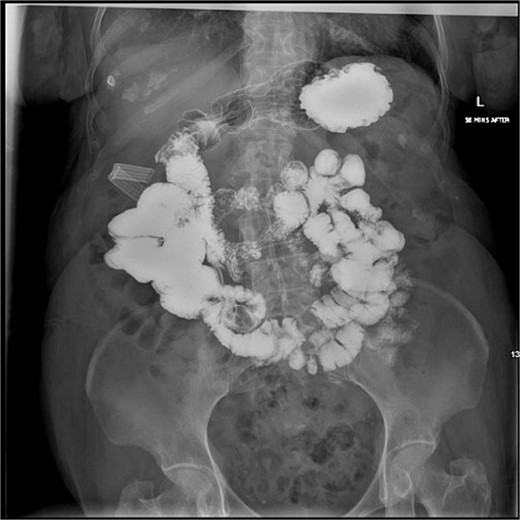

This is the case of an 86-year-old female with an independent baseline functional status and a history of hypertension and prior episodes of medically treated cholecystitis per patient preference. She presented to the Emergency Department at a public major tertiary care hospital for abdominal pain and was found to have a gallstone ileus. A CT scan showed: a gallstone in the jejunum causing a bowel obstruction proximally, pneumobilia, gallbladder wall edema, and pericholecystic fluid (Fig. 1). A nasogastric tube was placed for bowel decompression prior to proceeding for urgent operative exploration.

CT scan from the initial episode of gallstone ileus. A) Coronal CT: cholecystoduodenal fistula, B) Coronal CT: pneumobilia (superior, white dotted arrow) and air-filled gallbladder (inferior, green dotted arrow), impacted gallstone (solid white arrow), C) Axial CT: cholecystoduodenal fistula, D) Axial CT: impacted gallstone.